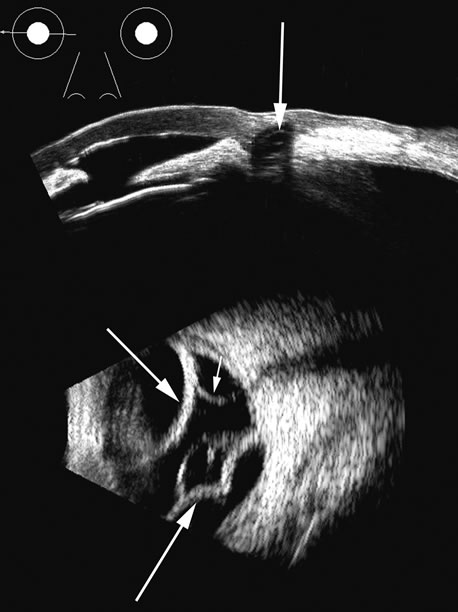

| Fresh blood in the vitreous may be acoustically clear since the red cells

may not have congealed sufficiently to form a good echo-producing

surface.8 A retracted “hyaloid” or posterior limiting membrane (PLM) of

the vitreous can be shown with most B-scan instruments, but

paradoxically a retracted vitreous may not be seen as well

with higher-resolution, more highly focused transducers because

they display less area of the reflective surface. Blood collected on

the surface of the PLM enhances this surface and may, in some cases, make

the PLM resemble a detached retina, since its anatomic dimensions

can be similar to the retina. Three differences may help distinguish the

two structures. First, kinetic scanning reveals a lack of attachment

at the optic nerve for a PLM. Second, the PLM is irregular in reflection

and thickness (usually thicker than the retina) between

the ora and the disc, and usually the surface cannot be traced forward

to the ora on the B-scan display. Third, the amplitude of the

echoes from the PLM is lower than from the retina, except when directly

perpendicular to the beam, where they may be similar in amplitude. Many

of these features of a PLM are demonstrated in Figure 7, whereas Figure 8 shows a typical detached retina. Hemorrhage shows good echogenic properties and presents a typical highly reflective vitreous body (Figs. 9 and 10). Asteroid hyalosis may resemble a vitreous hemorrhage except that the individual calcium deposits are even more reflective than hemorrhage and usually there is a clear anechoic zone between the retina and the retracted primary vitreous (Fig. 11). Synchysis scintillans is another condition with highly reflective regions in the vitreous due to cholesterol crystals. It is identifiable by the kinetic scan pattern of floating “snowflakes” that settle when the eye stops moving, just like the snowflakes in a child's snow globe. Since the “normal” vitreous is usually dissolved in this condition, the echoes come to rest on the retinal surface when the eye stops moving. An area or region of attachment of presumed vitreous to the ocular wall can be seen with kinetic scans and may indicate an area of stress or possible retinal tear. In diabetic retinopathy with proliferative membranes, the vitreous is often attached to a membrane, producing a typical cross-shaped elevation on a scan through the long axis of the proliferans. Right-angle or three-dimensional scans show the folded nature of the retinitis proliferans membrane (see Fig. 13). |